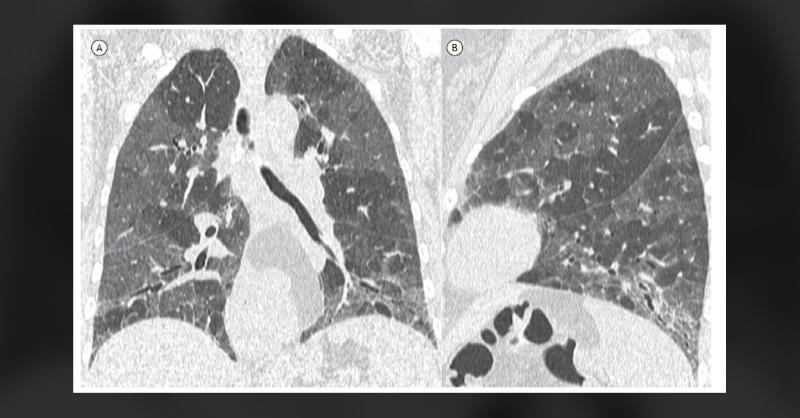

Lung Pattern of Patient With Hypersensitivity Pneumonitis

A 48-year-old woman came in reporting fatigue, worsening shortness of breath, a persistent dry cough, and significant weight loss of 16 kilograms over the span of a year. CT imaging of her lungs revealed abnormalities consistent with lung tissue attenuation. While there were no observable changes in pulmonary blood vessel patterns or arterial flow